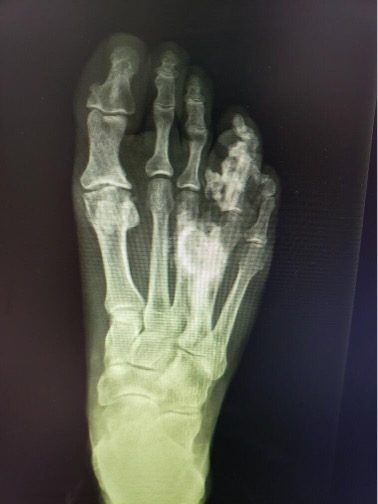

On plain films, one could note radiodensity at the right fourth metatarsal shaft and right fourth proximal and middle phalanges with significant hypertrophic osseous formation of the right fourth metatarsal shaft and right fourth proximal phalanx. The fourth digit appeared pedunculated from the medial aspect of the base of the proximal phalanx with possible synostosis to the right third metatarsal shaft.

Magnetic resonance imaging (MRI) showed abnormal cortical thickening, expansion, and irregularity of the fourth ray, including involvement of the metatarsal and all the phalanges. Based on radiography there was involvement of the calcaneus (seen on lateral view). Plain film radiography revealed involvement of the calcaneus, seen on the lateral view. There was a soft tissue mass noted at the distal aspect of the fourth ray. There was ossification in the plantar soft tissues contiguous with the fourth ray hyperostosis.

These findings were felt to be most consistent with a dysplastic bone disease; likely melorheostosis. The treatment team then decided to pursue surgical intervention.